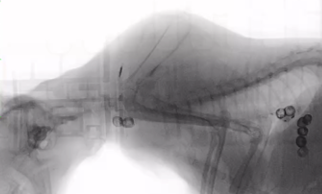

- 猫用ストマックケア: 食べ物の通り道(食道)のスムーズな通過を助けるため、独自の「粒形状」を採用。吐き戻しなどの消化器症状の軽減を図っています。